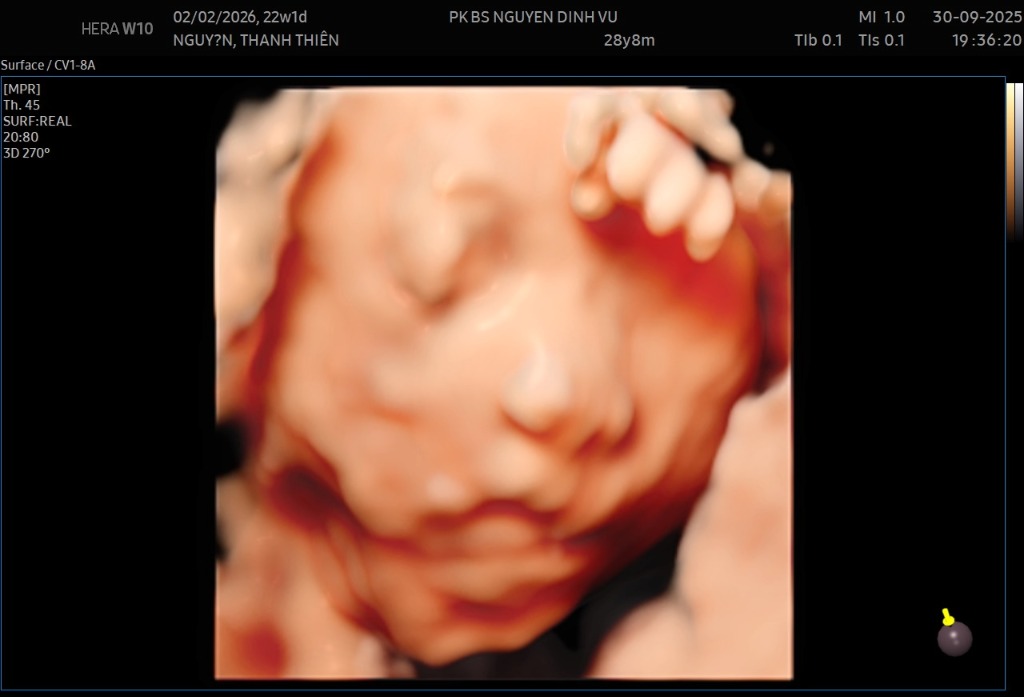

Nguyễn Thanh Thiên